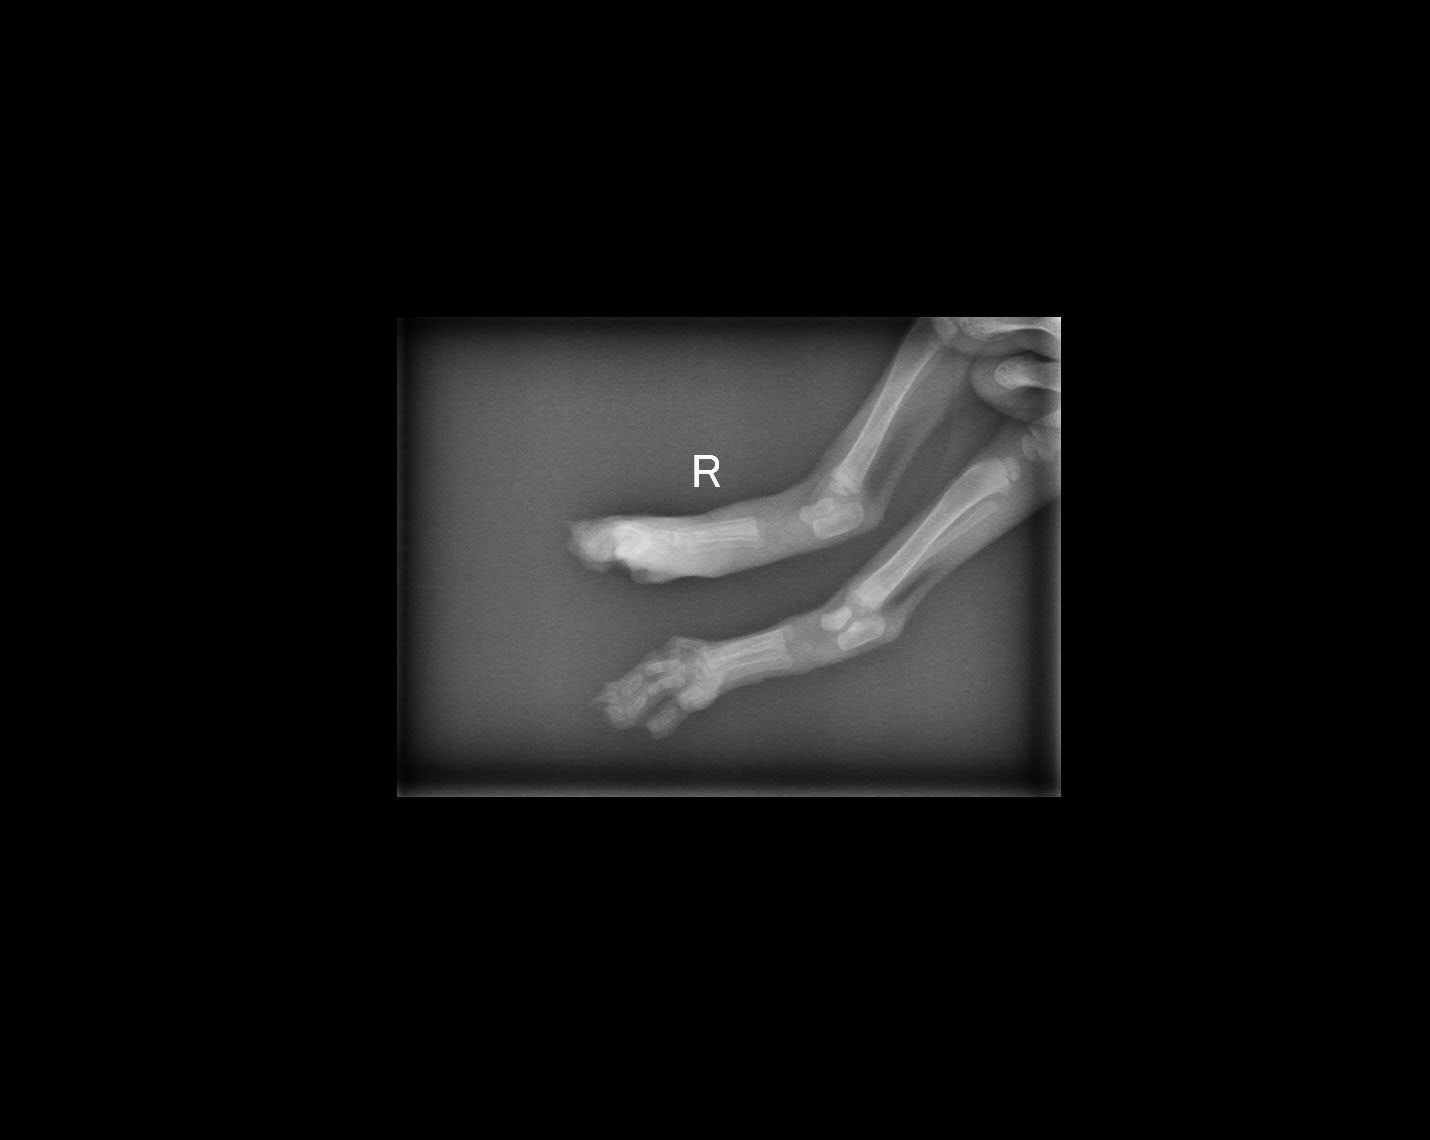

主題: 感染腳掌腫大的小虎斑 申請者姓名: 張菱予 花色: 申請日期: 2020-07-19 16:01:00 申請者部落格: https://www.facebook.com/clyanal 申請者臉書網址: https://www.facebook.com/clyanal 所在縣市/合作醫院: 高雄市/小新動物醫院 治療費用: 18350元 需求人數: 43人 已結案 (2024-05-31 18:15:34) 報名人員: 黃茂強(已付款)、Panda Song x2(已付款)、Panda Song x2、Aimee Chen、Ivy(已付款)、Tiffany(已付款)、AJu x2(已付款)、小乖(已付款)、ICheng Hu x2(已付款)、Ting Ju x2(已付款)、瑞妮(已付款)、kei(已付款)、無名氏(已付款)、雲荻(已付款)、May x4(已付款)、儒曉 x2(已付款)、儒曉 x2、柴犬(已付款)、俊藤劍(已付款)、艾曼達 x2(已付款)、Mido、Mido(已付款)、Shelley Hu(已付款)、Rene(已付款)、Lulu(已付款)、Wei(已付款)、Ikea(已付款)、Sofi lo x6(已付款)、謝小姐 x2(已付款)、李瓶(已付款)、小玉(已付款)、kino(已付款)、 候補人員: 動物病情說明: 下著大雨的午後,兩隻可憐的小虎斑在車子下喵喵叫,費了一些功夫撈到他們,發現其中一隻的腳掌異常腫大,趕緊送院治療,希望能控制感染不要再讓範圍擴大∼

送院後透過抗生素治療讓腫大的腳掌稍微消腫,這時才發現小虎斑的腳掌被不明物體壓出一道裂痕,才造成蜂窩性組織炎感染~但是壓到的腳掌及三腳指組織已經壞死,並且持續腫脹,考量到小虎斑年紀太小暫時無法進行手術,故醫生決定先做傷口清創進行治療!約住院一個月後,小虎斑壞死的組織已自行脫落,剩餘的腳指組織醫生判斷尚能使用,故不進行截肢手術,但是壞死組織脫落後仍有大範圍傷口需要每日包紮換藥,考量到年紀以及之前感染狀況,醫生建議留院治療到傷口結紮癒合後再出院~動物近況說明: 非常感謝小新動物醫院細心照顧,小虎斑不僅不需截肢,還在院內吃的頭好壯壯,雖然失去左後腳三分之二的腳掌,但是行動上完全沒有問題!也感謝捐款幫助小虎斑的大家,他雖然失去腳掌,但是得到的是你們滿滿的愛與關懷,未來他會帶著大家的祝福順利的找到新家並快樂的生活!